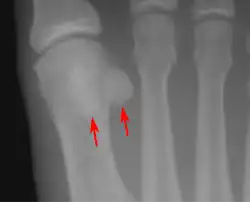

![]() Sesamoid bones at the distal end of the first metatarsal bone of the foot. | |

- In the foot—the first metatarsal bone usually has two sesamoid bones at its connection to the big toe (both within the tendon of flexor hallucis brevis).[10] One is found on the lateral side of the first metatarsal while the other is found on the medial side. In some people, only a single sesamoid is found on the first metatarsal bone.

Lateral view.[11]